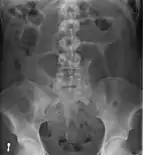

- Abdominal x-ray – tire-like shadow arising from right iliac fossa and passing to left

Coffee bean sign in a person with sigmoid volvulus

An x-ray of a person with a small bowel volvulus.

Plain X ray of a cecal volvulus